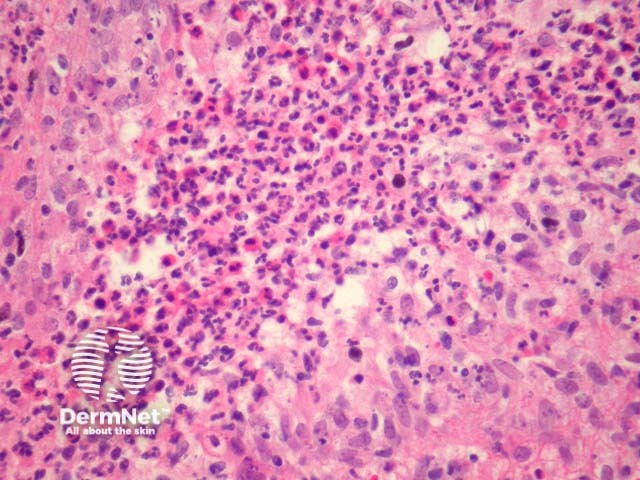

In sporotrichosis, sections show epidermal hyperplasia overlying a marked acute and chronic inflammatory response (figure 1). Higher power shows the inflammation infiltrates the overlying epidermis (figure 2). The infiltrate is polymorphous with giant cells, histiocytes, and focal neutrophilic microabscess formation (figure 3). Careful examination of multiple sections is required to identify the causative organisms (figure 4, arrows).

Figure 3